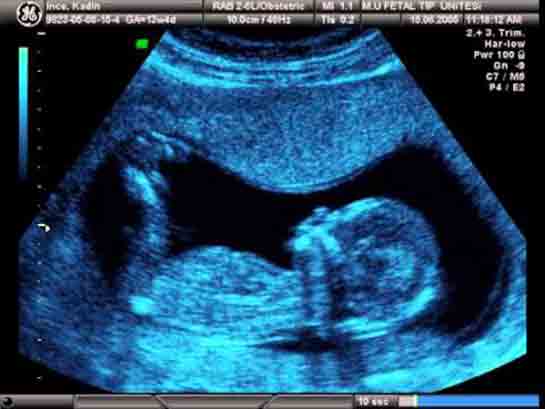

24 Haftalık Gebelik 24 haftalık gebelik, bir hamilelik sürecinin ikinci trimesterinin sonlarına yaklaşan bir dönemi temsil eder. Bu dönem, hem anne hem de bebek açısından önemli fizyolojik değişimlerin yaşandığı bir süreçtir. Bu yazıda, 24 haftalık gebelik döneminde meydana gelen gelişmeler, sağlık önerileri ve dikkat edilmesi gereken noktalar detaylı bir şekilde ele alınacaktır. Fetal Gelişim 24 haftalık gebelikte fetusun gelişimi önemli bir aşamaya ulaşmıştır. Bu dönemde, fetusun boyu yaklaşık 30 cm, ağırlığı ise 600-700 gram civarındadır. Aşağıda, fetal gelişim ile ilgili bazı önemli noktalar belirtilmiştir:

Bebek Gelişimi